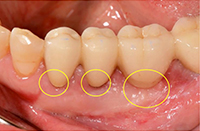

治療前の状態です。

歯ぐきが退縮し(歯ぐきが下がり)、歯の根が露出しています。 -

歯ぐきが退縮している部分に、結合組織を移植します。

*遊離歯肉移植術(FGG)では歯ぐきを移 植しますが、結合組織移植術(CTG)は結 合組織を移植します。